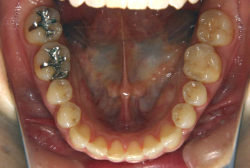

「左奥歯でものが噛めない」という主訴で来院したケースです。診断の結果、基本的には「叢生」という隙間が足りないと言うことが原因の凸凹症例でしたが、左下の乳歯が高校生になってもまだ残存している状態で、そのせいで噛み合わせが極端に悪くなっていました。

検査の結果、乳歯の下には後継ぎの永久歯が先天的に欠如していました。配列の凸凹が厳しく非抜歯で矯正することは難しく、仮に無理をして非抜歯治療をしても後々「後戻り」が懸念されることから、このような症例の場合は通常、上下顎左右第一小臼歯を抜歯させていただくのですが、左下は乳歯を抜歯して、第一小臼歯は残すことにしました。これで結果として、小臼歯部を上下左右で一つずつ減らしたのと同じ状況になります。治療後は歯並びが綺麗になっただけでなく、噛み合わせ的にも正しい状態が確立しています。

このように、先天的に永久歯が足りないという症例は最近増えています。親知らずはなくても特に問題になりませんが、その他の歯が足りないと言うのは審美的にも機能的にも重大な障害となります。しかし、矯正治療を正しく行えば、結果として歯がすべてあった場合と全く同じ仕上げにすることも可能です。